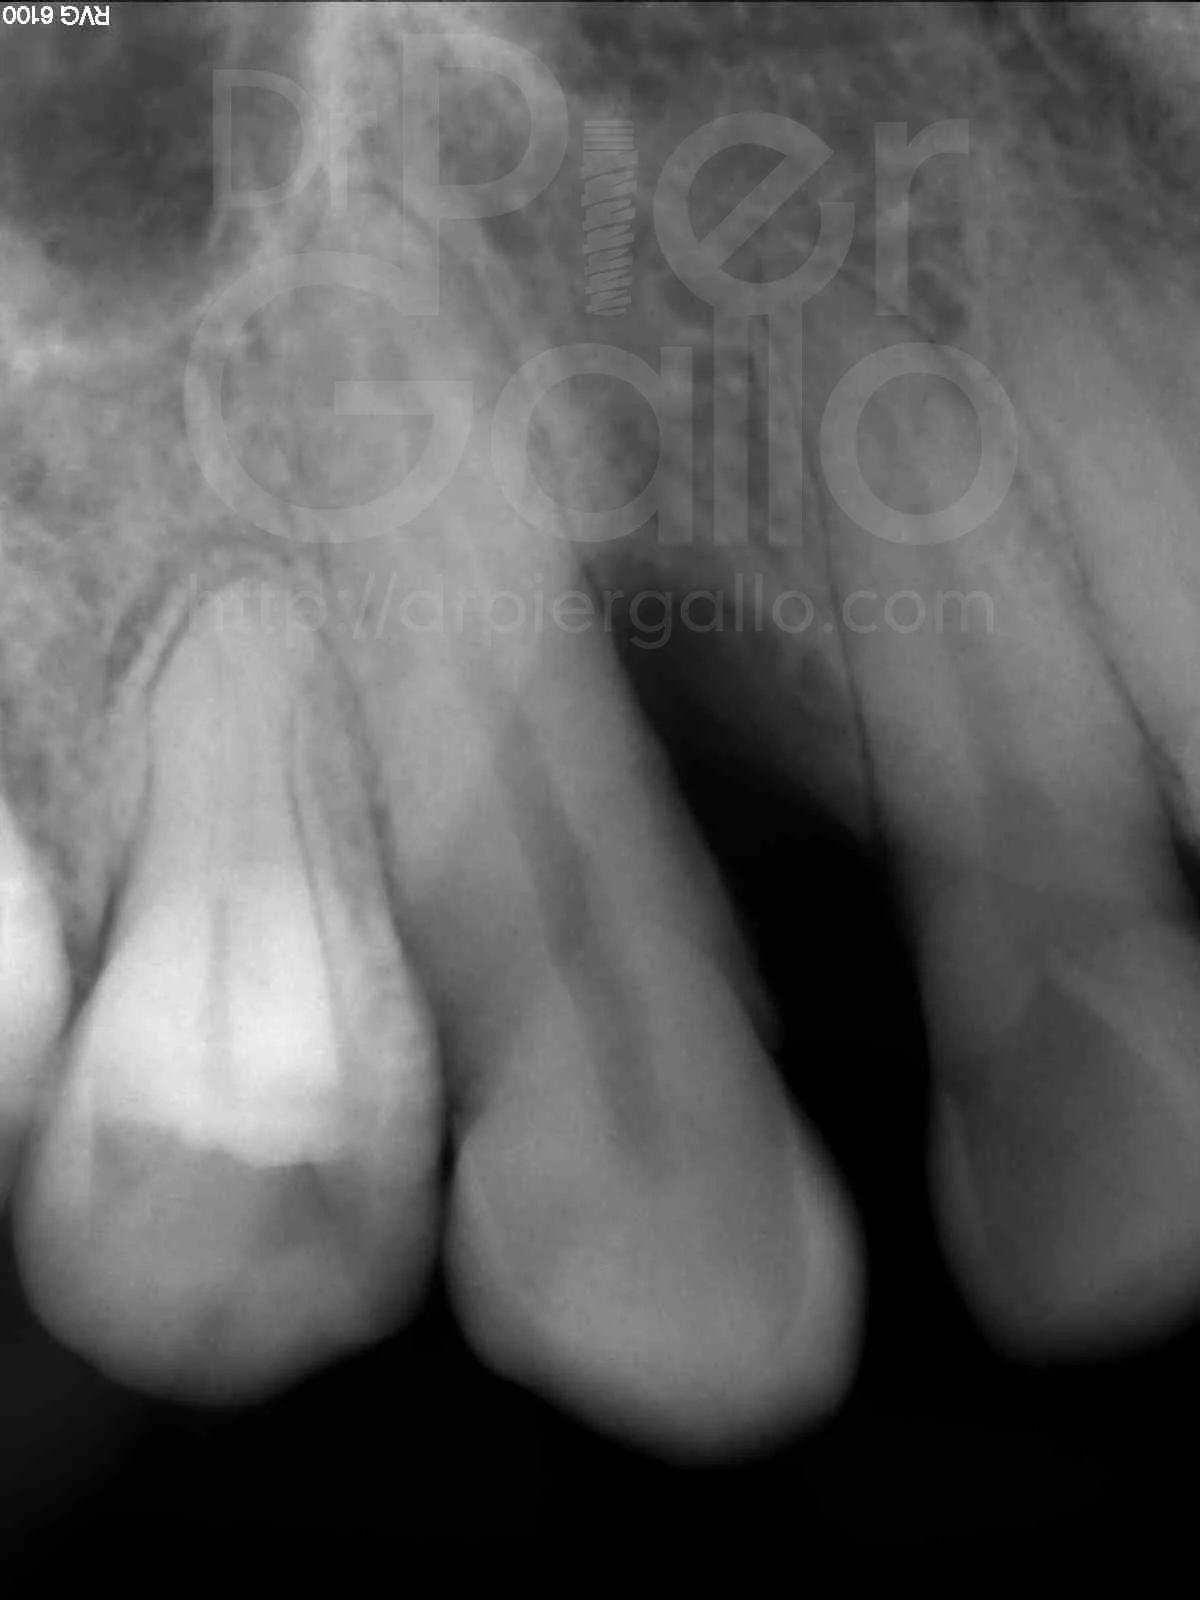

Paciente de 36 años de edad que presenta una pérdida ósea vertical a nivel del 13, con profundidad de bolsa de 15mm, se programa para hacer una Regeneración Tisular Guiada con rhPDGF-BB.